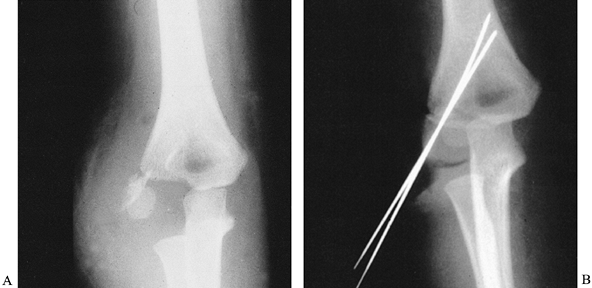

usually occur as the result of a fall on an outstretched hand and

of their metaphyseal component (Fig. 164.4A),

|  |

| Figure 164.4. Lateral condylar fracture of the humerus treated by open reduction and pinning. A: AP radiograph of acute fracture. B: Fracture is anatomical after fixation with two K-wires. |

condylar fractures is displacement, either acute or progressive, of the

arthrography. We generally perform open reduction because the joint

surface is often remarkably displaced.

Fix the fracture with two K-wires (Fig. 164.4B).